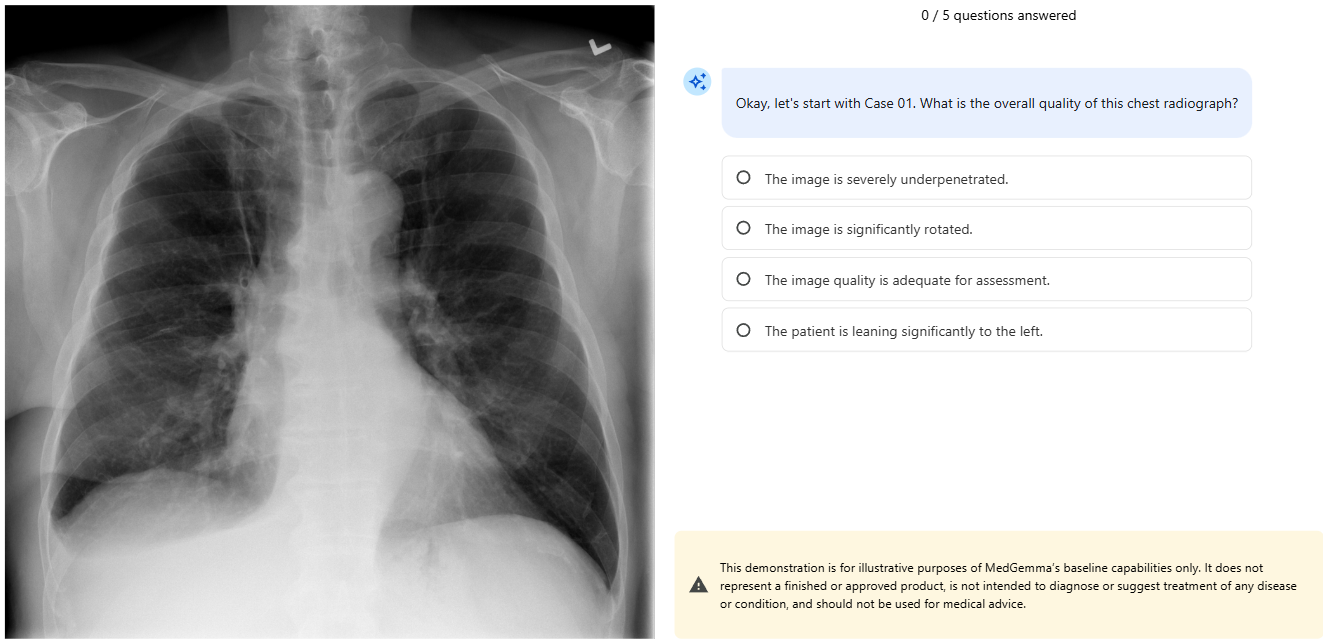

18). Case 01 또는 Case 02 중에서 하나의 이미지를 고르시고, 그 이미지의 하단에 있는 파란색 버튼(Launch)을 눌러주세요! Launch 글자 밑에 The WHO manual of diagnostic imaging을 누르면 WHO의 방사선 이미지 진단 매뉴얼을 보실 수 있습니다. MedGemma를 RAG 기술을 활용해서 이 매뉴얼에서 정보를 가져와서 답을 준다고 합니다.

20). MedGemma가 방사선 이미지에 대한 질문을 우리에게 합니다. 우리에게 답을 고르라고 요청합니다.